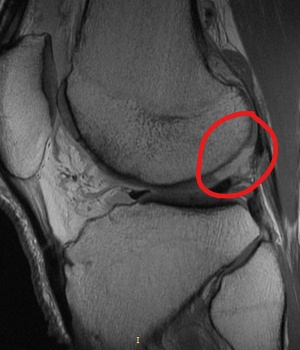

Before and After Image

Pre and Post Op MRI Showing Healed Cartilage Lesion